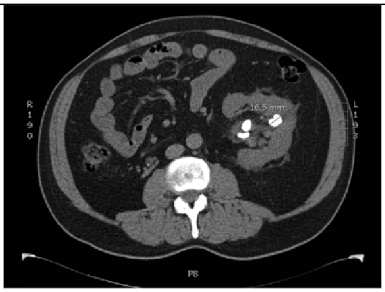

2.6.1. Test Procedure

The stress test involved simulating varying numbers of concurrent users querying the system. For each LLM, we executed 20 clinically relevant prompts, as shown in (Table A2) in the Appendix A. For each VLM, 10 different images with 2 prompts per image resulting in a total of 20 prompts per model were tested. The specific prompts used are listed in (Table A3) in the Appendix A. We tested user loads of 10, 20, 30, 40, 50, 75, 100, 125, and 150 users. In order to measure the robustness of the container as well as the robustness of JAVIS, this experiment queried the JAVIS back-end to measure the complete roundtrip response times. This approach ensured that the test accurately reflected real-world usage scenarios, including the overhead of back-end processing and model orchestration.